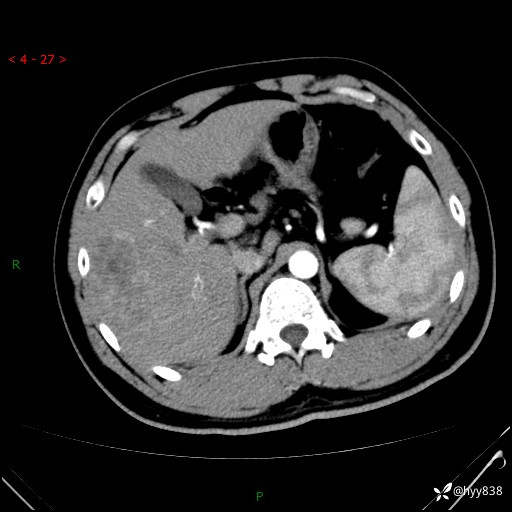

肝脏CT平扫

img